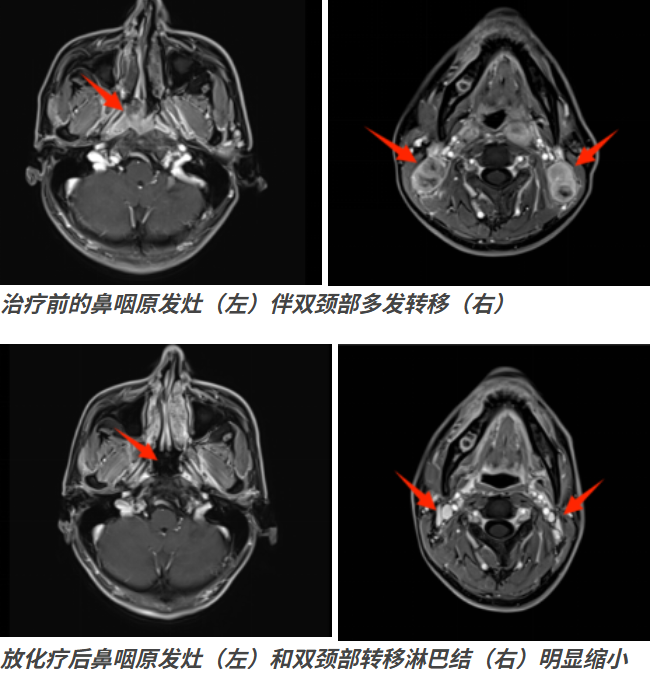

随后,刘先生转诊至我院鼻咽癌诊治中心,邱素芳主任医师团队为他展开全面检查:鼻咽部MRI显示,鼻咽恶性肿瘤已累及咽后间隙、翼内肌、枕骨斜坡等多处结构,双侧颈部及锁骨上还有多发淋巴结转移;活检病理确诊为非角化性未分化型癌,EB病毒DNA拷贝数也显著升高。经多学科专家会诊,他被明确诊断为鼻咽癌Ⅲ期(AJCC第九版),初步排除远处转移,为后续治疗留足了机会。

针对患者病情,医疗团队制定了4周期的化疗和35次调强放疗的综合方案,放疗靶区精准覆盖鼻咽原发灶及双侧颈部转移区域,确保在控制肿瘤的同时,最大程度保护周围正常组织。

日前,患者到医院复查,影像学显示肿瘤体积明显缩小,各项指标均朝着好的方向发展。